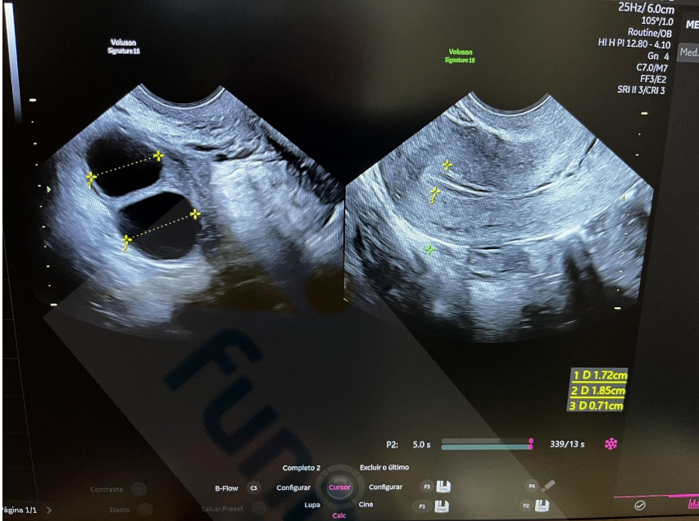

Analise a imagem abaixo de um exame de ultrassonografia transvaginal.

Considerando a análise desse exame, a paciente:

I. Está no período periovulatório.

II. Pode estar realizando estimulação ovariana.

III. Está em uso de contraceptivo hormonal combinado.

IV. Pode estar com muco cervical aumentado pela fase do ciclo em que se encontra.

Quais estão corretas?